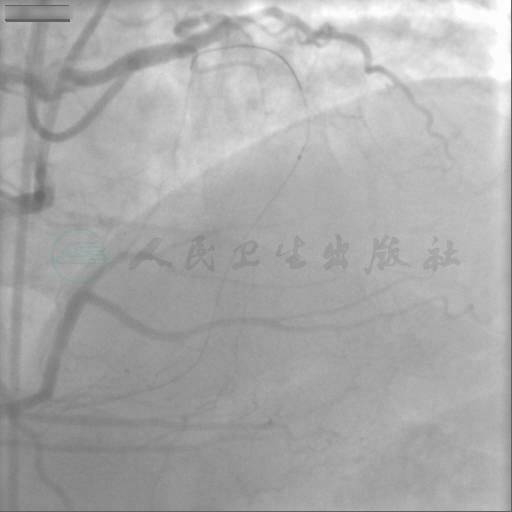

冠脉CTA:前降支自开口完全闭塞,闭塞近端可见高位间隔支(图1)。

图1 冠脉CTA显示前降支开口位置